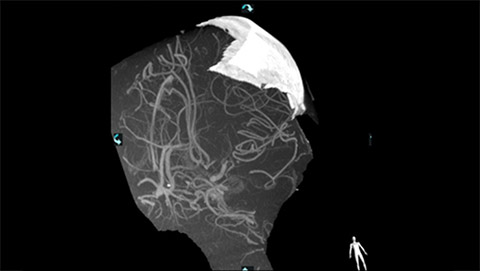

VasoCT (Allura X-ray system with dedicated EPX settings + XperCT + intravenous contrast injection) provides high-resolution imaging of intracranial arteries to help visualize location, size, and direction of an occlusion in case of Ischemic Stroke.

MR/CT Roadmap visualizes lesion boundaries and corresponding vascularization, while helping you to manage X-ray dose and contrast medium. 3D Roadmap provides full 3D view for dynamic guidance of guidewire and catheter navigation through complex vascular lesions.